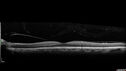

Branch Retinal Vein Occlusion with Venous Macroaneurysm (collateral)280 views66 year old female Did not notice vision loss in the right eye. The right eye has been a little worse than the left but now is much worse. Picked up during annual eye examination. VA had been 20/20 in 5 years ago.

History of brain and spinal cord radiation 1986 for T-cell lymphoma. Now with breast cancer, ablation for tachycardia, HTN

VA OD 6/200, OS 20/32Oct 16, 2021